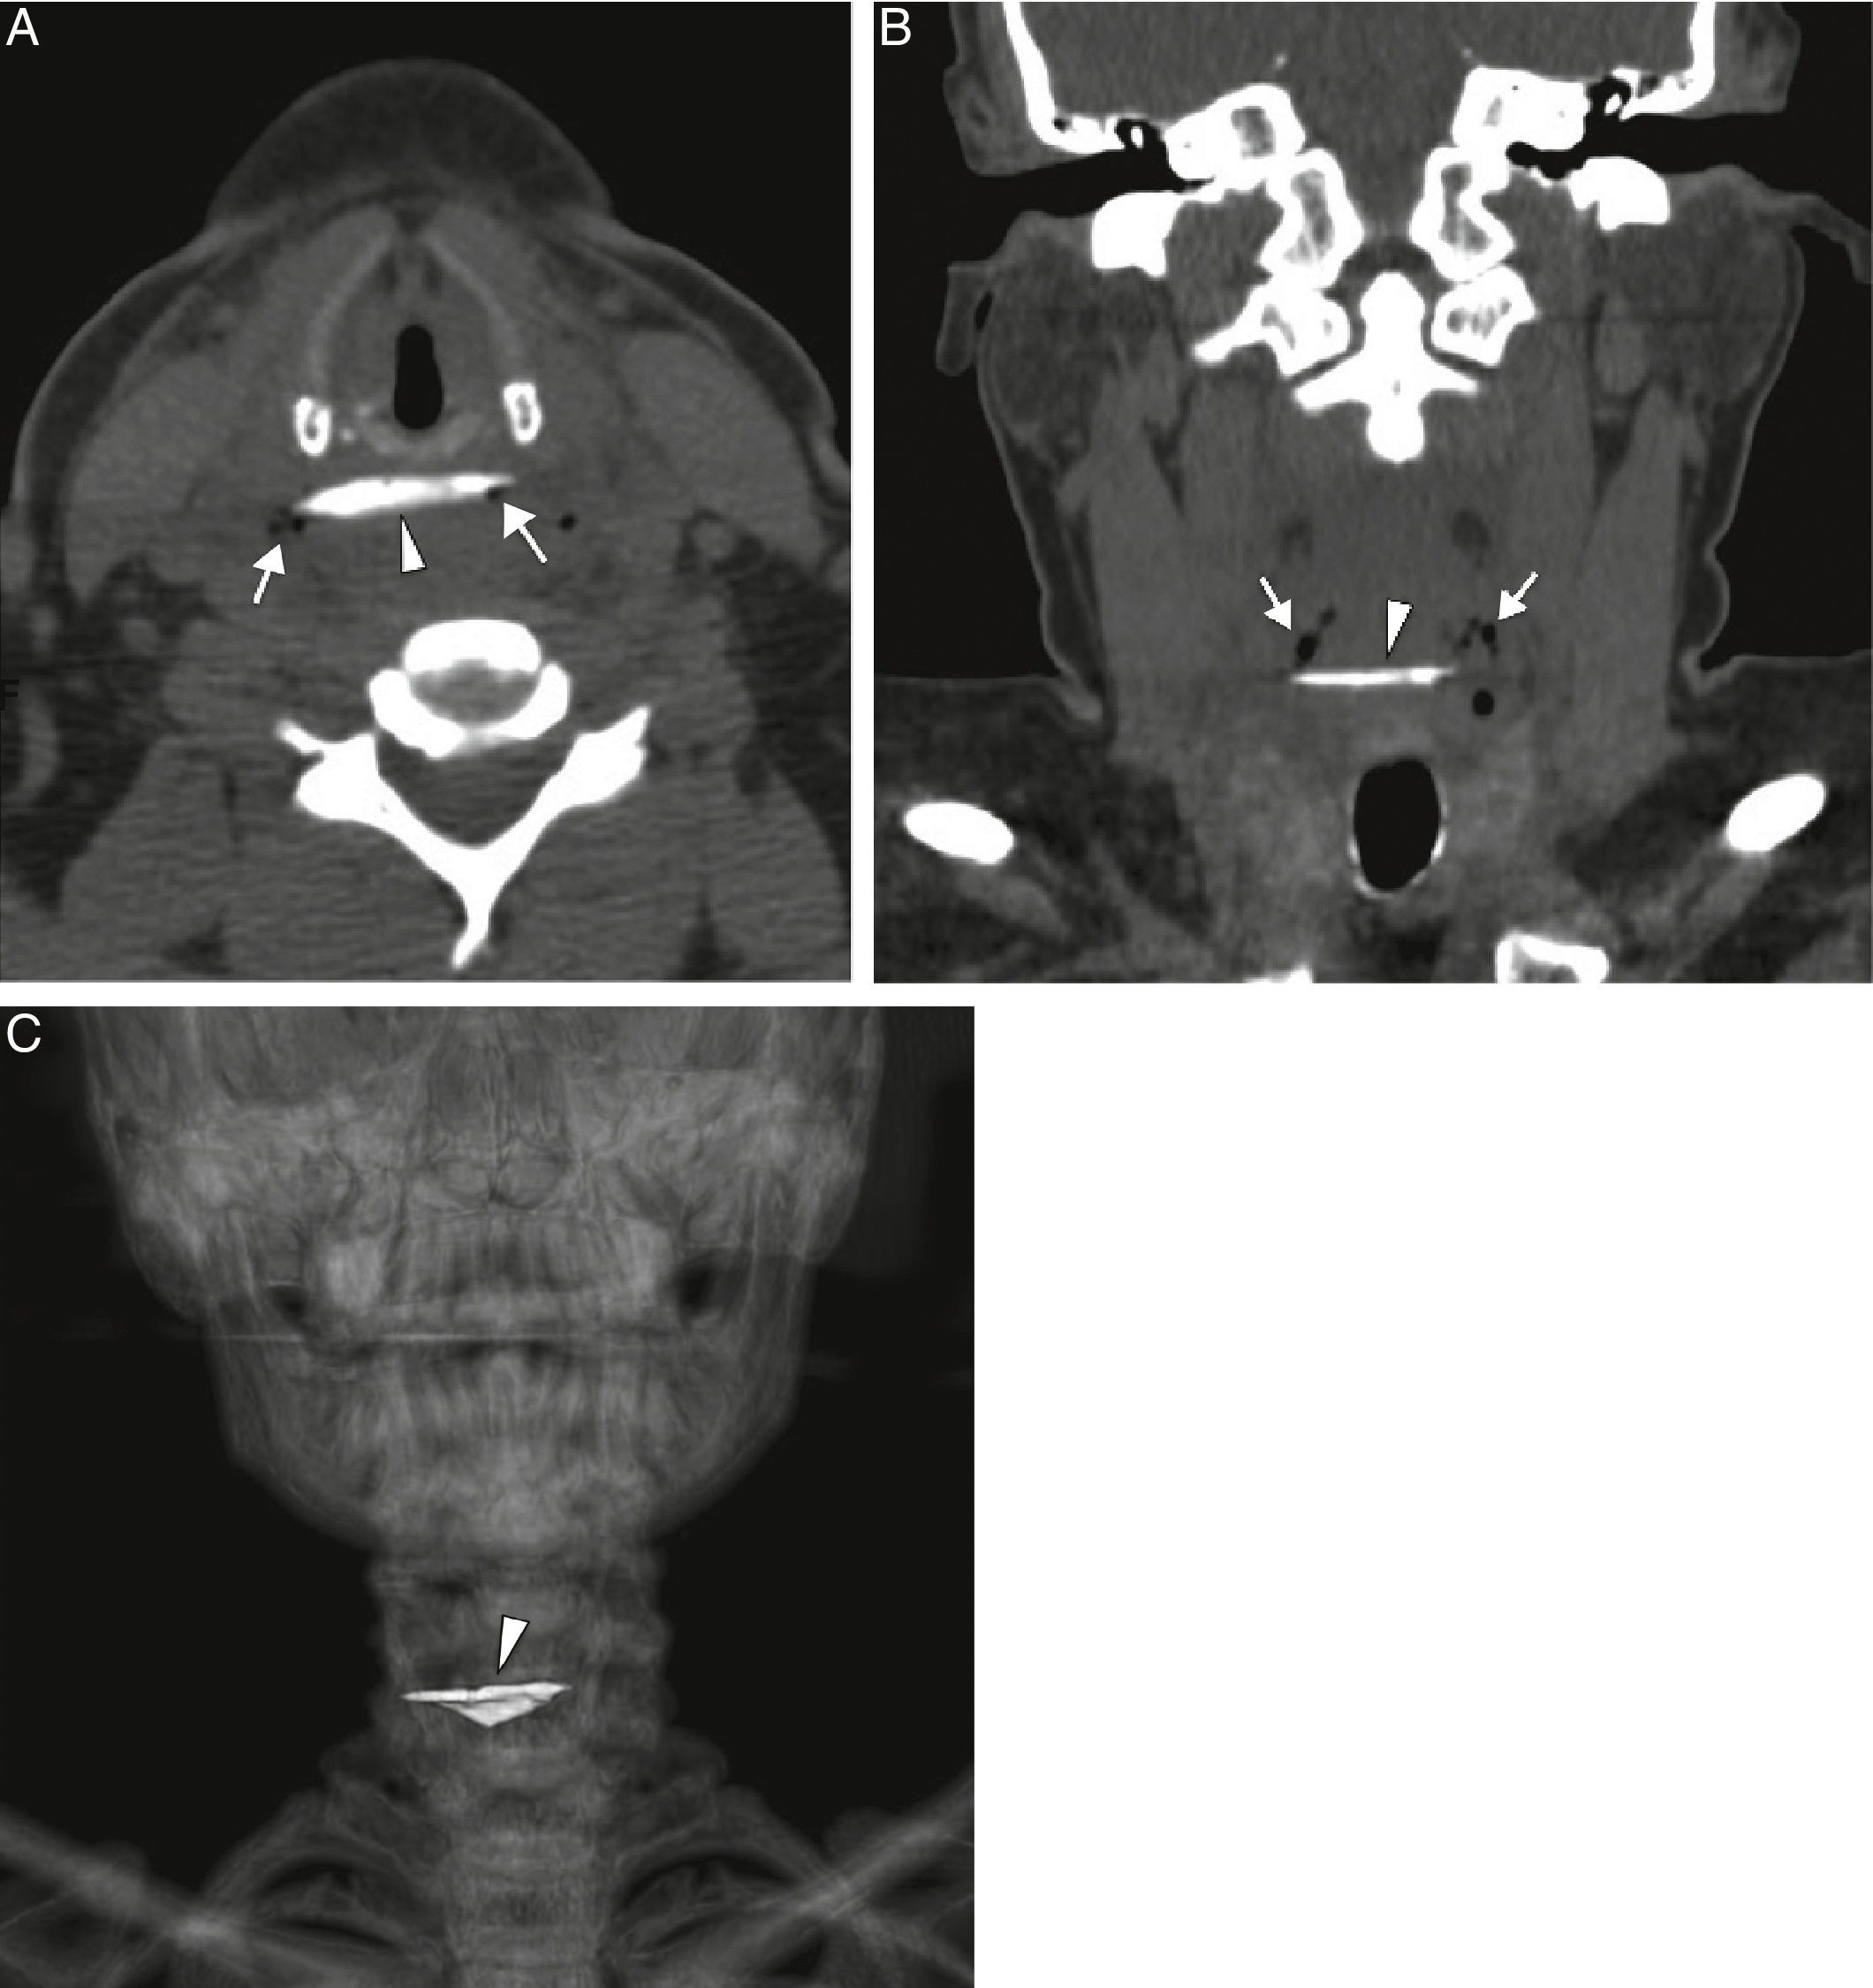

Una mujer de 43 años de edad llegó a nuestro departamento de urgencias, habiendo ingerido un hueso de pollo. Sus síntomas clínicos eran babeo ligero y sangre en la saliva. Se sometió al paciente a un examen de fibra óptica, que reveló un hueso como cuerpo extraño en la mucosa del esófago proximal, que parecía estar causando una perforación parcial (fig. 1). Una tomografía computarizada confirmó la presencia de un cuerpo extraño con forma de hueso, con bordes puntiagudos a la altura del esófago proximal, con perforación limitada (fig. 2A-C). Se realizó una extirpación endoscópica urgente del cuerpo extraño, sin complicaciones, y se confirmó que el objeto era un pedazo de hueso de pollo afilado (fig. 3).

A) Imágenes axial y B) coronal de la tomografía computarizada que muestran el cuerpo extraño con forma de hueso (punta de flecha) a la altura del esófago proximal, con pequeñas burbujas de aire en el tejido blando (flechas), como indicación de una perforación limitada. C) La reconstrucción de imagen del renderizado de volumen 3D de la tomografía computarizada coronal del cuerpo extraño con forma de hueso (punta de flecha).